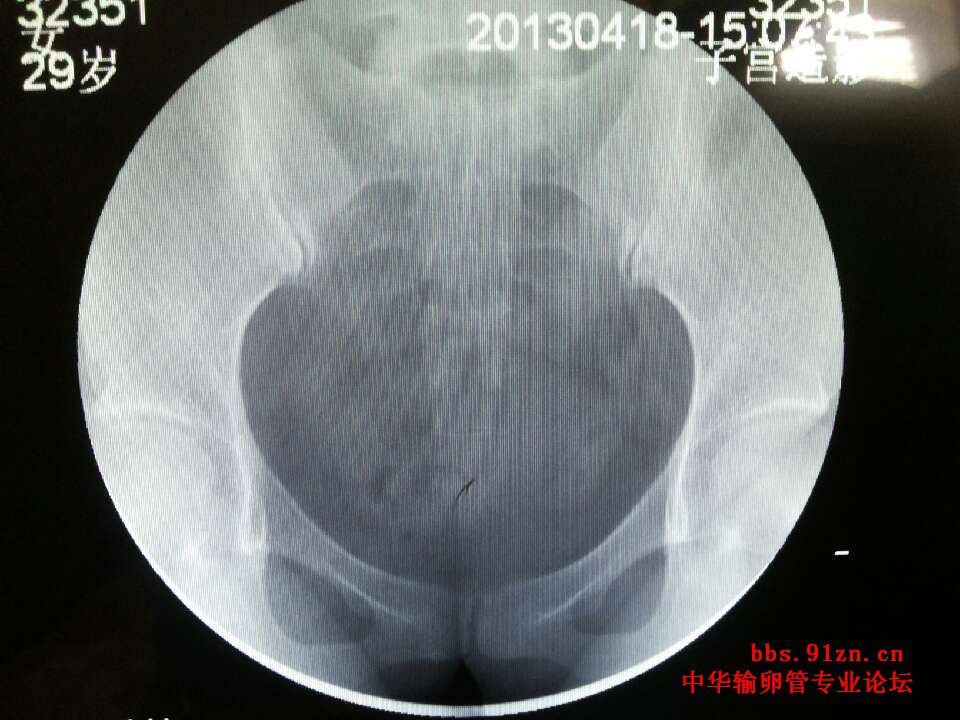

请大夫看看输卵管造影片

年龄:(29 )岁 ;近期查出多囊卵巢综合症,左右各11.12个卵泡,小于6mm 已经试孕( 半)年; 平时月经周期不准,月经持续3 天; 既往怀孕(1   )次,流产( 1)次药流,最近一次流产距今(5  )年; 男方的精液检查结果( a+b=40%,a18%);

您的片子上没有标左右,您有一侧没有显影,显示阻塞,或者是切除过一侧输卵管,另一侧虽然通畅,但是略有些粘连,但是您不怀孕的主要原因是多囊的问题,卵巢不排卵肯定怀不上孕,您这种该情况可以手术治疗,一是治疗多囊,二是探查另一侧不通的,通的那侧粘连可以分解开,没有其他问题术后第二个月就有自然受孕的机会。